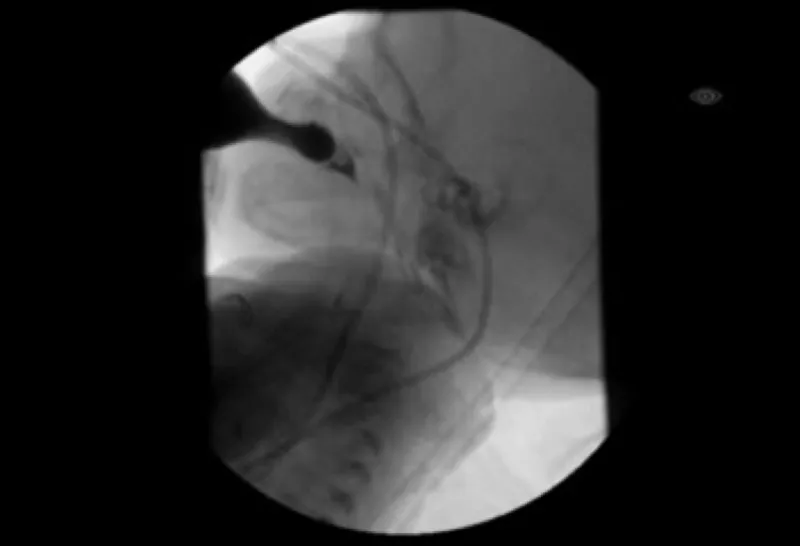

Infants may have a weak suck, which can lead to prolonged feedings or poor weight gain. Some may require special bottles or nipples to help them drink enough. They may also have liquid come out of their nose when feeding or spitting up, which can be uncomfortable but is not dangerous. Infants may have difficulty coordinating their sucking with swallowing and breathing, which can lead to liquid entering the lungs when swallowing, called aspiration. Older children can also have signs of aspiration, such as coughing, choking, and congestion when drinking or recurrent respiratory infections. If aspiration is suspected, a Modified Barium Swallow study will likely be recommended (Figure 2). This is a dynamic X-ray study that assesses your child’s swallow function while they eat and drink.

How a MBS is performed: A MBS is a test used to look for aspiration. Fluoroscopy, similar to an X-ray, is used to watch a child feed on different thicknesses of liquid. This test is performed in the Department of Radiology with a feeding therapist and radiologist. (Photo courtesy of Katie Engstler, SLP)

During the MBS, the liquid a child drinks includes a special dye that can be seen on X-ray. We watch as the dye moves from the bottle or cup, though the mouth and throat, and can see if it is entering the child’s airway (aspiration) while he or she feeds. (Photo courtesy of Katie Engstler, SLP)